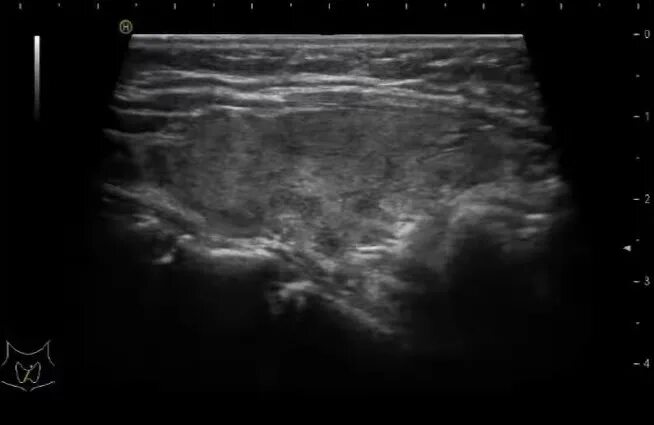

На фоне диффузных изменений